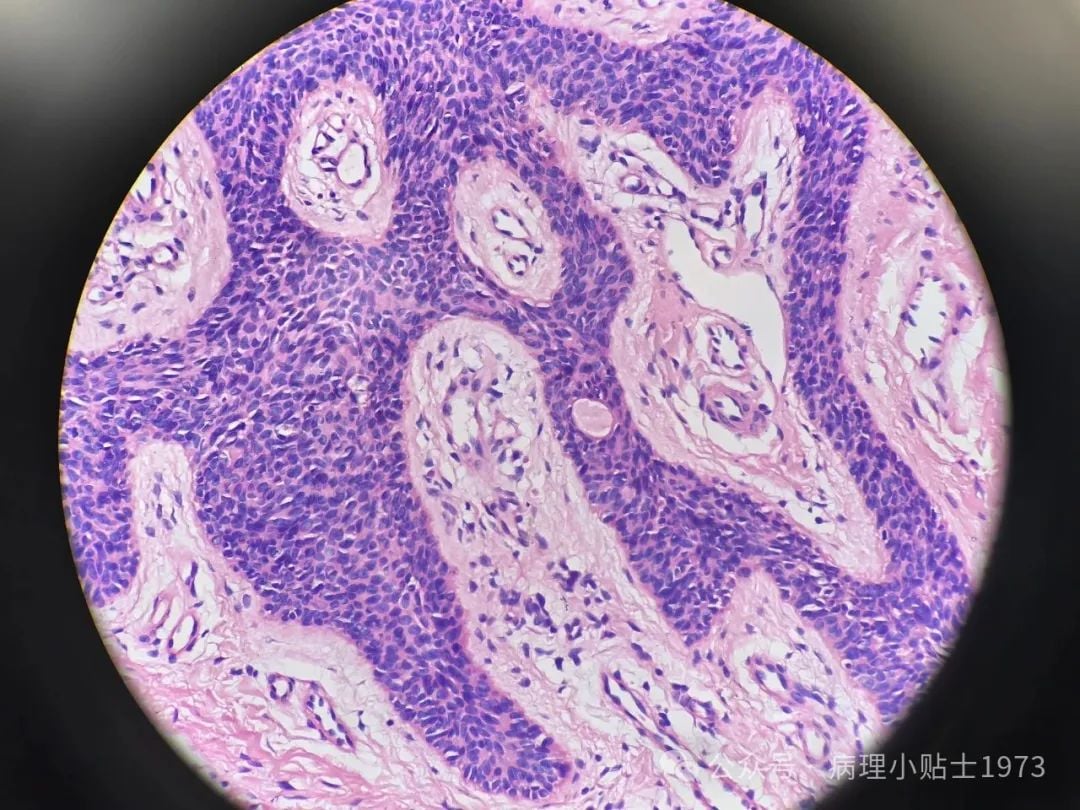

- 镜下观察: 在显微镜下,可以看到肿瘤由形态温和、大小一致的细胞构成,并形成了类似汗腺导管的结构。细胞没有明显的恶性特征,如异型性和快速分裂,这进一步证实了其良性性质。